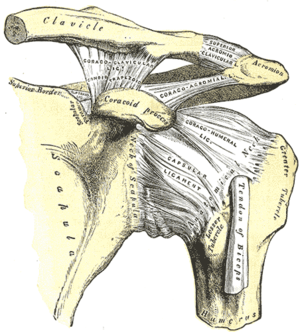

The upper or proximal extremity of the humerus consists of the bone's large rounded head joined to the body by a constricted portion called the neck, and two eminences, the greater and lesser tubercles.

Humeral head

The head (caput humeri), is nearly hemispherical in form. It is directed upward, medialward, and a little backward, and articulates with the glenoid cavity of the scapula to form the glenohumeral joint (shoulder joint). The circumference of its articular surface is slightly constricted and is termed the anatomical neck, in contradistinction to a constriction below the tubercles called the surgical neck which is frequently the seat of fracture. Fracture of the anatomical neck rarely occurs.[1] The diameter of the humeral head is generally larger in men than in women.

Anatomical neck

The anatomical neck (collum anatomicum) is obliquely directed, forming an obtuse angle with the body. It is best marked in the lower half of its circumference; in the upper half it is represented by a narrow groove separating the head from the tubercles. It affords attachment to the articular capsule of the shoulder-joint, and is perforated by numerous vascular foramina. Fracture of the anatomical neck rarely occurs.[1]

The anatomical neck of the humerus is an indentation distal to the head of the humerus on which the articular capsule attaches.

Tubercles

The greater tubercle (tuberculum majus; greater tuberosity) is situated lateral to the head and lesser tubercle, and just lateral to the anatomical neck. Its upper surface is rounded and marked by three flat impressions: the highest of these gives insertion to the supraspinatus muscle; the middle to the infraspinatus muscle; the lowest one, and the body of the bone for about 2.5 cm. below it, to the teres minor muscle. The lateral surface of the greater tubercle is convex, rough, and continuous with the lateral surface of the body.[1]

The lesser tuberosity or lesser tubercle (tuberculum minus; lesser tuberosity), although smaller, is more prominent than the greater: it is situated in front, and is directed medialward and forward. Above and in front it presents an impression for the insertion of the tendon of the subscapularis muscle.[1]

Bicipital groove

The tubercles are separated from each other by a deep groove, the bicipital groove (intertubercular groove), which lodges the long tendon of the biceps brachii muscle and transmits a branch of the anterior humeral circumflex artery to the shoulder-joint. It runs obliquely downward, and ends near the junction of the upper with the middle third of the bone. In the fresh state its upper part is covered with a thin layer of cartilage, lined by a prolongation of the synovial membrane of the shoulder-joint; its lower portion gives insertion to the tendon of the latissimus dorsi muscle. It is deep and narrow above, and becomes shallow and a little broader as it descends. Its lips are called, respectively, the crests of the greater and lesser tubercles (bicipital ridges), and form the upper parts of the anterior and medial borders of the body of the bone.[1]